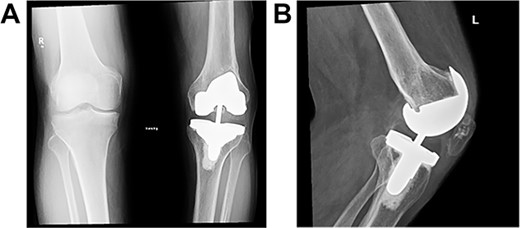

Long weight-bearing knee radiographs showed severe osteoarthritic changes, 18° knee genuvarum and extension deformity of the left distal femur (Fig. 2). Skyline view showed severe arthritic changes (Fig. 3).

Preoperative plain radiographs; (A) severe osteoarthritic changes affecting the left knee with narrowing of the medial knee joint compartment; (B) left femur with dorsal angulation above the condyles and severe patella baja.